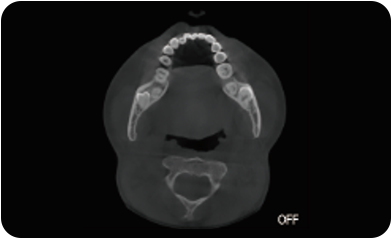

支持局部超清三维显示

局部超清显示、 移动视野摄片

可根据临床需求任意调整成像区域大小实现局部超清三维显示

临床样片